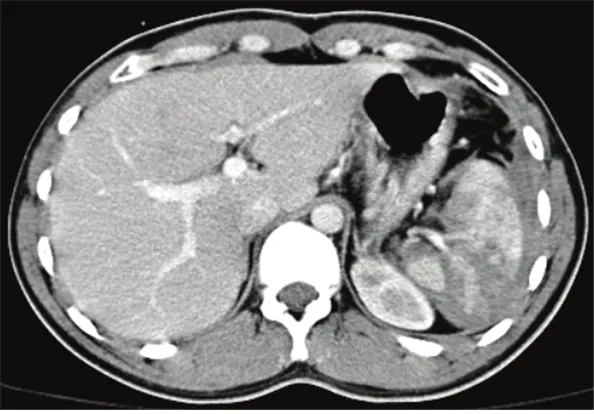

31세 여성이 자전거를 타다가 넘어져 응급실로 이송되었다. 의식은 맑았으며, 내원 당시 혈압은 110/70 mmHg, 맥박은 88회/분, 호흡수는 22회/분, 체온은 36.5℃이었다. 지속적으로 복부 통증을 호소하여 복부 컴퓨터단층촬영을 시행한 결과이다. 45분 후 재측정한 생체 징후는 혈압 78/50 mmHg, 맥박 122회/분으로 확인되었다. 적절한 치료방법은 무엇인가?

비장의 일부에서 저음영 소견을 보이며 V/S unstable하여 응급 수술이 필요하다.

• 내원 당시 V/S stable하며 복막 자극 징후는 없어 APCT를 촬영하였으며 비장 저음영 소견이 관찰된다.

• 검사 후 비장 손상이 확인되며 혈압 감소, 맥박, 호흡수 증가의 저혈량성 쇼크 로 진행하는 양상이므로, 응급으로 비장 절제술을 시행해야 한다.